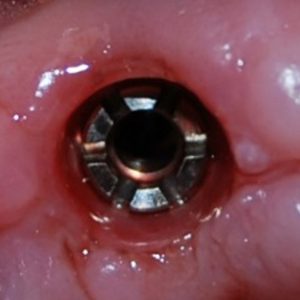

По факту же… помимо конической и плоской платформы, существует еще десяток разнообразных типов ортопедических интерфейсов. К примеру, Zimmer Spline:

или Ankylos:

У каждого типа ортопедической платформы есть свои плюсы и минусы, и было бы глупо утверждать, что какая-то из платформ круче, чем все остальные. Несмотря на простоту, тема ортопедических интерфейсов настолько обширная, что я решил вынести ее в отдельную статью, дабы навсегда положить конец войне конуса и шестигранника. Просто подписывайтесь и следите за обновлениями.